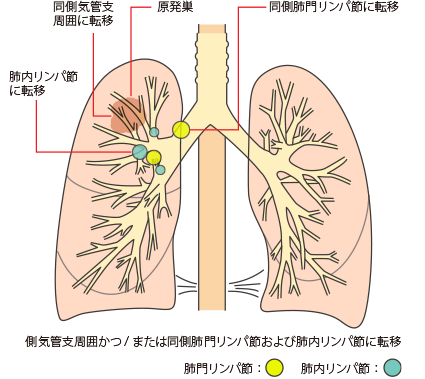

TNM分類:N-リンパ節転移

リンパ節への転移の有無

NX

所属リンパ節評価不能

N0

所属リンパ節転移なし

N1

同側の気管支周囲かつ/または同側肺門、肺内リンパ節への転移で原発腫瘍の直接浸潤を含める

N2

同側縦隔かつ/または気管分岐下リンパ節への転移

N3

対側縦隔、対側肺門、同側あるいは対側の前斜角筋、鎖骨上窩リンパ節への転移

肺がんがリンパ節に転移した場合は

人間の体には、血管と同じように全身をめぐるリンパ系というネットワークがあります。リンパ系は、体中に張りめぐらされたリンパ管と、リンパ管の集まるリンパ節からできており、細菌やがん細胞をやっつける免疫機能を担っています。

がんが大きくなって近くのリンパ節に広がると、がん細胞がリンパ管を通って、別のリンパ節へ転移するリンパ行性転移が起こります。肺には多くのリンパ節があるため、肺がんはリンパ行性転移を起こしやすいがんといえます。

リンパ節転移が起こると、リンパ節が腫れて周囲の神経や器官を圧迫するため、いろいろな症状が起こります。

リンパ節への転移とステージ・症状

がんの部位に応じて転移しやすいリンパ節がグループ化されており、それを所属リンパ節といいます。

肺がんでは、肺門(肺の入り口周辺)リンパ節、肺内(肺の中)リンパ節、縦隔(左右の肺に挟まれた空間)リンパ節という3つのグループに分かれます。

所属リンパ節への転移の段階はN因子(NX、N0、N1、N2、N3)で表され、病期(ステージ)を決める要素の一つです。数字が大きくなるほど、転移の範囲が広がっていることを示します。

肺がんのリンパ節転移をN因子で表すと、

NXは、所属リンパ節に転移があるかどうか評価できないことです。所属リンパ節がすでに摘出されているときなどにNXとなります。

N0は、所属リンパ節に転移がないことです。

N1は、最初にできたがん(原発巣)と同じ側の気管支周囲や肺門または肺内リンパ節に転移があることです。

N2は、原発巣と同じ側の縦隔リンパ節または気管支が分かれる部位のリンパ節に転移があることです。

N3は、原発巣とは反対側の縦隔リンパ節や肺門リンパ節または鎖骨上のリンパ節、首の付け根にあるリンパ節に転移があることです。

肺の入り口や気管支周辺のリンパ節に転移があると、咳がでてくることがあります。

気管支前リンパ節に転移が起こると、上大静脈が圧迫されるので上半身のむくみや息切れ、頭痛、めまい、眠気などの上大静脈症候群があらわれることがあります。

左側の気管支リンパ節に転移が起こると、かすれ声が起こることがあります。

リンパ節転移があると、病期(ステージ)はII期以上と判定されます。